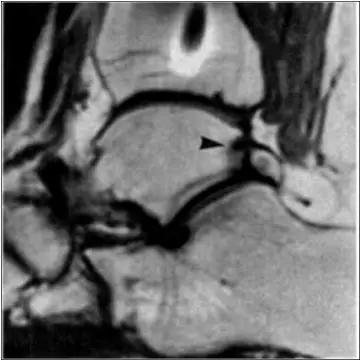

- MRI 检查示距后三角骨及周围软组织有水肿信号,距后三角骨和距骨之间正常的低信号纤维连接中断,出现液性信号。

3、MR表现:

- 三角籽骨或距骨后三角结构模糊和变形,T1WI信号降低, T2WI信号升高,

- 周围脂肪水肿,

- 踇趾长屈肌腱信号升高,见鞘膜积液,

- 胫骨后下跟骨上缘骨结构形态变化和信号异常,

- 三角籽骨和距骨退行性囊变。